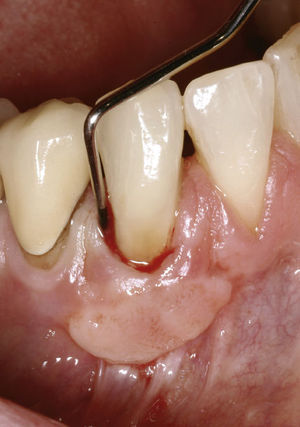

SintomatologíaLas reabsorciones externas cursan de forma asintomática o con molestias leves. El aspecto de los dientes no suele estar alterado y en casos raros se observan signos periodontales locales como una tumefacción o inflamación de la encía. La prueba de sensibilidad suele ser negativa, pero también puede ser positiva sobre todo al principio del proceso, y la prueba de percusión puede arrojar un resultado anómalo en determinadas circunstancias. No se aprecia movilidad elevada del diente afectado. Las profundidades de sondaje determinadas alrededor de todo el perímetro del diente están aumentadas en la zona de la laguna de reabsorción y permiten deducir parámetros como la posición y las dimensiones del defecto (fig. 5). Pueden producirse también exudaciones.

Características radiográficasDesde el punto de vista radiográfico, las reabsorciones externas (fig. 6) se caracterizan por los siguientes signos:

Luz del conducto radicular no dilatada.

Imagen radiolúcida en la zona radicular de límites irregulares.

Localización asimétrica.

La localización cambia con la proyección radiológica excéntrica.

Desaparición localizada del espacio periodontal.